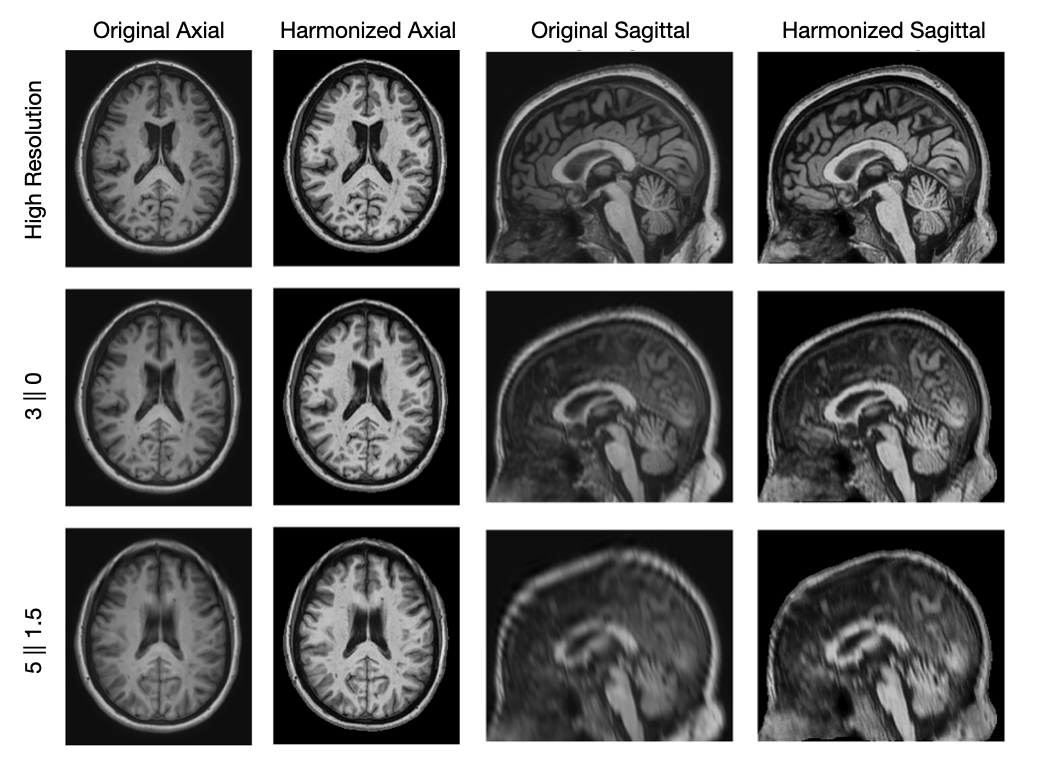

Figure 2 shows the original and harmonized registered T1w images at HR and two simulated LRs demonstrating the impact of resolution degradation. We show a LR image simulating an axial acquisition at a resolution of , which is the best 2D resolution we investigate and a LR image simulating a sagittal acquisition at a resolution of , which is the worst resolution we investigate. As the resolution gets worse, we observe that the image appears more blurry due to the slice thickness. The T2w and T2w-FLAIR images behave similarly to the T1w images.